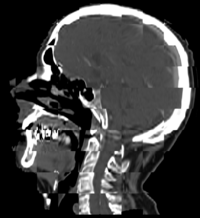

Adaptive Radiotherapy for Head, Neck and ThoraxWe proposed an algorithm to include prior knowledge in previously segmented anatomical structures to help in the segmentation of the next structure. This will add enough prior information to allow the Graph Cuts algorithm to segment structures with fuzzy boundaries. More... New: I. Kolesov, V. Mohan, G. Sharp and A. Tannenbaum. Coupled Segmentation for Anatomical Structures by Combining Shape and Relational Spatial Information. MTNS 2010.